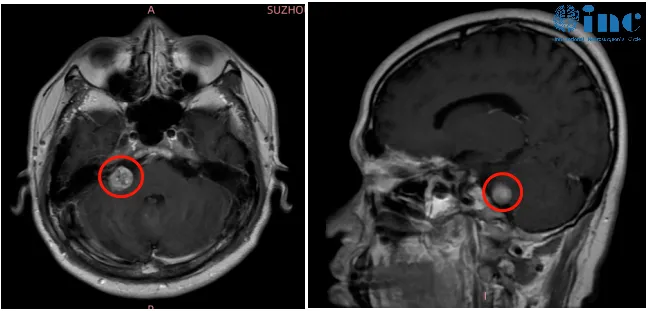

住院接受两周药物治疗后,其听力奇迹般恢复至20-30分贝。正当全家放松之际,头颅增强MRI检查发现新问题:右侧桥小脑角区存在结节,考虑听神经瘤,且肿瘤大部分深嵌于内听道内。

"内听道深部听神经瘤的手术难度极高,堪比刀尖操作。"医生的解释让高老师陷入两难抉择:肿瘤与面听神经紧密缠绕,要实现完全切除必须磨除部分骨质,极易损伤神经导致永久性面瘫;若选择保守治疗,肿瘤持续生长会反复诱发突发性耳聋,甚至影响平衡功能。

2022年春季,高老师成功接受巴教授主刀的示范手术。手术采用国际公认的"内听道磨除术+膜内切除术+无热伤切瘤法"技术组合,该技术经过40余年临床验证,核心理念为"精准分离、微创切除"——通过磨除内听道骨质暴露深部肿瘤,在神经监测仪实时引导下沿肿瘤包膜内逐步剥离,避免损伤面听神经。